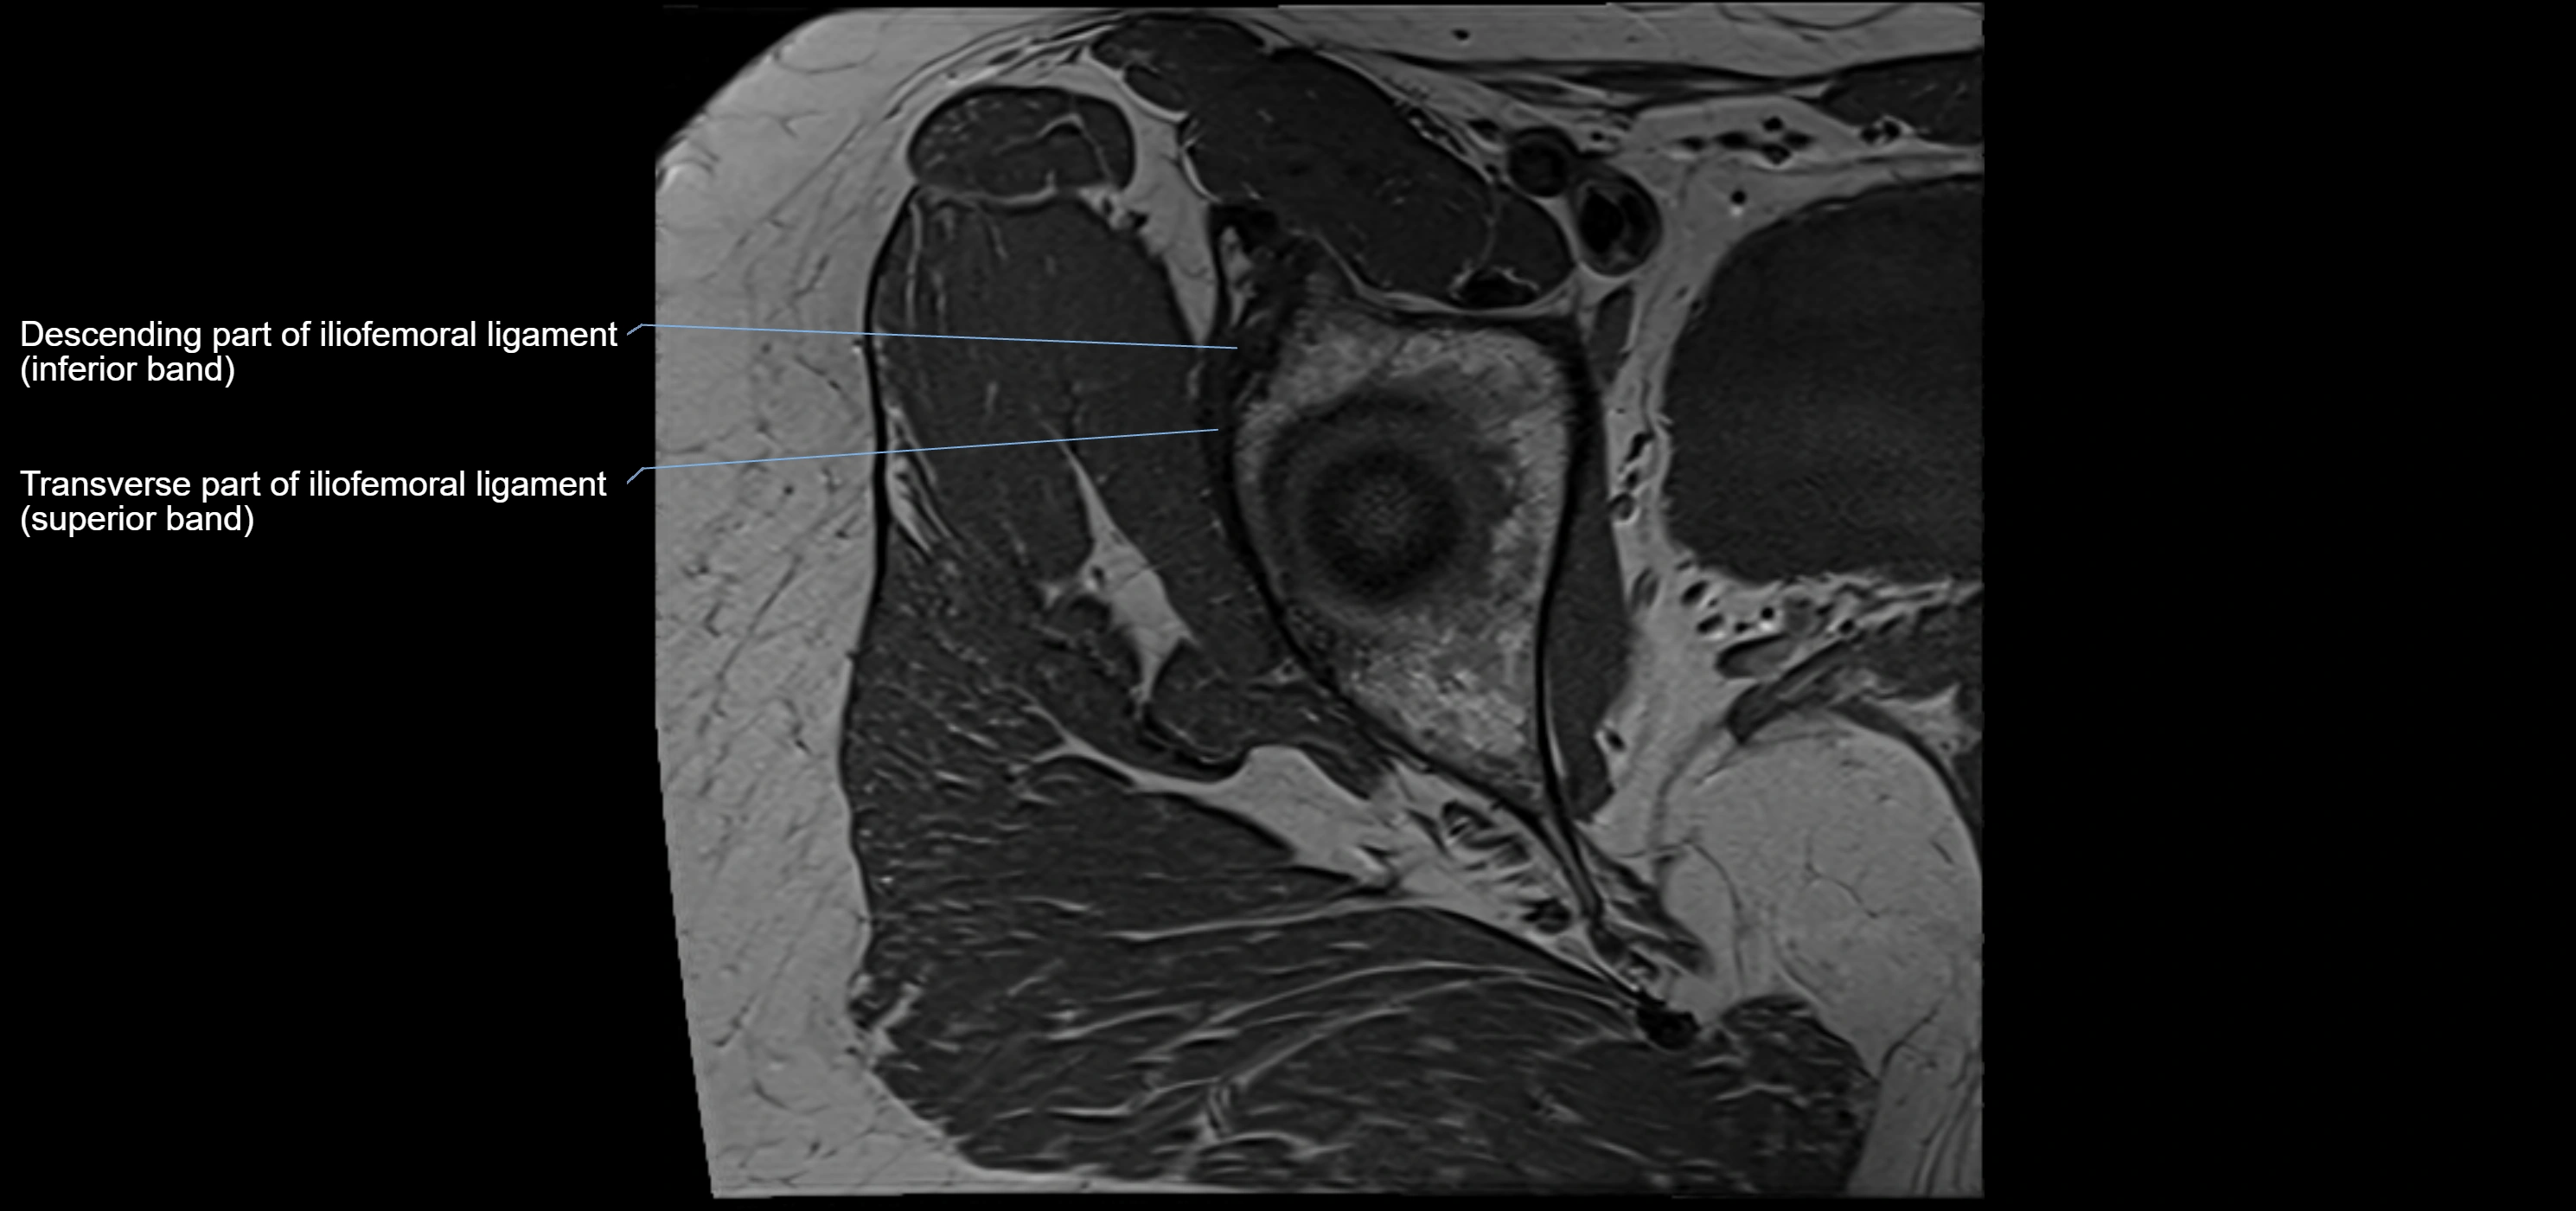

The acetabular labrum is a fibrocartilaginous ring that surrounds the rim of the acetabulum in the hip joint. It deepens the hip socket, increases joint stability, and maintains a suction seal that preserves negative intra-articular pressure. Structurally, the labrum transitions from hyaline cartilage of the acetabulum to dense fibrocartilage at its free edge.

It is triangular in cross-section, with its base attached to the acetabular rim and its apex projecting toward the femoral head. The labrum is most robust superiorly and anteriorly, where load bearing is greatest, and relatively thinner inferiorly.

Structure and Relations

• Superior and anterior labrum: thickest portions, stabilizing against anterior dislocation

MRI Appearance

T2-weighted images:

• Labrum: low signal intensity (dark)

• Joint fluid: bright, making labral tears visible as fluid extending into or around labrum

MRI image

image